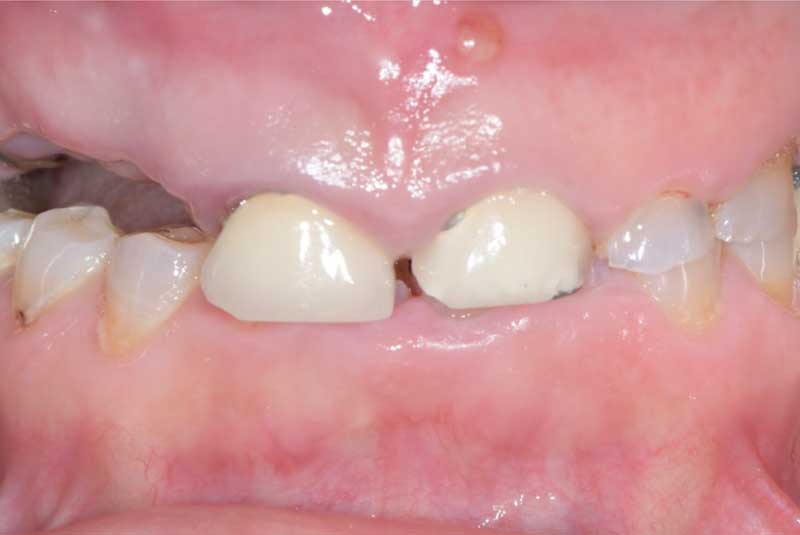

Implant crowns (#7-10) Before & After